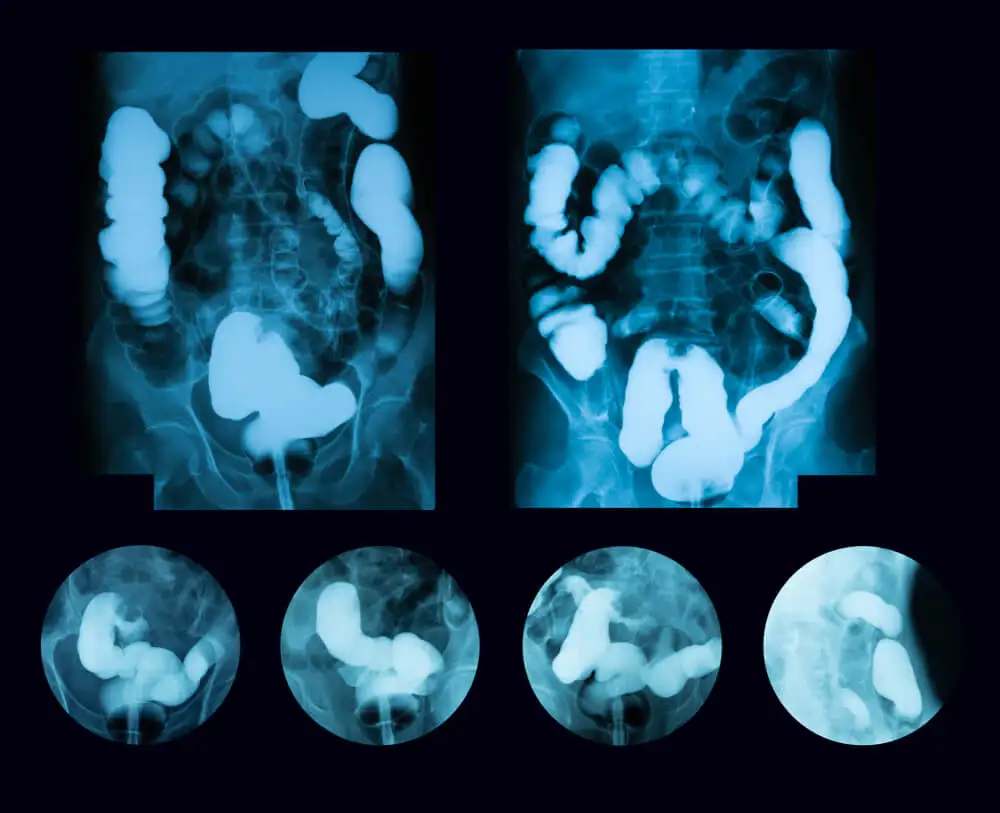

Para diagnosticar o megacólon tóxico, o médico levará em consideração os sintomas e perguntará sobre o histórico de doença inflamatória intestinal. Em seguida, ele fará um exame físico no qual sentirá o abdômen para verificar se há dor.

Ele também ouvirá a área abdominal com o estetoscópio para ouvir os sons intestinais. Provavelmente, ele pedirá alguns exames para confirmar o diagnóstico, como os seguintes:

- Raio-x abdominal.

- Tomografia computadorizada de abdômen.